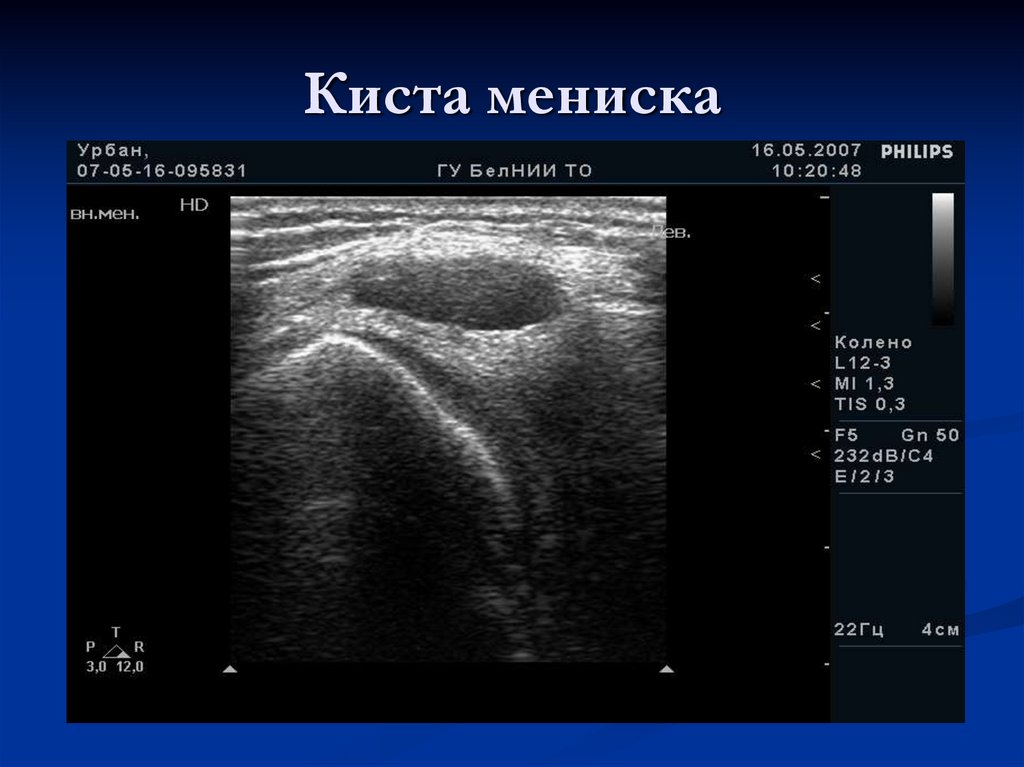

Киста мениска